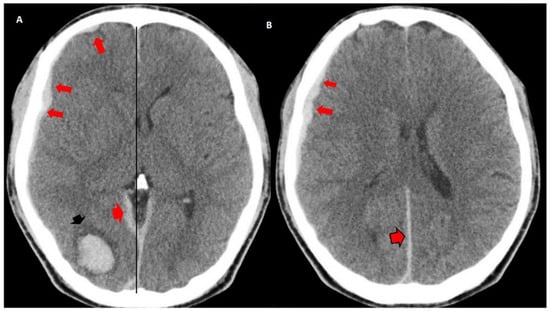

3.2. Imaging Studies